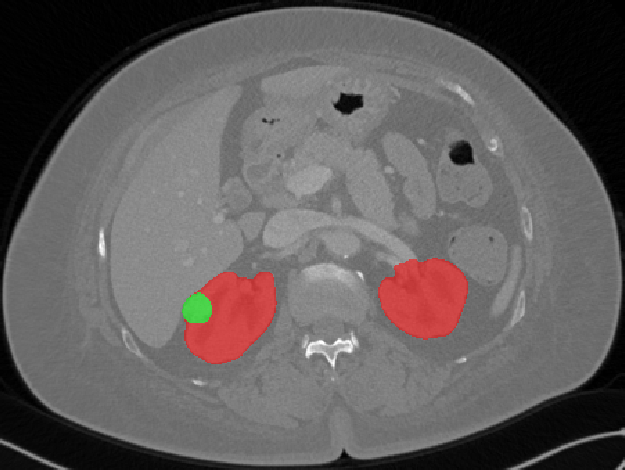

Edge-Aware 3D Image Segmentation Networks

[91]: Automated segmentation of kidneys and kidney tumors is an important step in quantifying the tumor’s morphometrical details to monitor the progression of the disease and accurately compare decisions regarding the kidney tumor treatment. Manual delineation techniques are often tedious, error-prone and require expert knowledge for creating unambiguous representation of kidneys and kidney tumors segmentation. We propose a 3D end-to-end edge-aware FCN for reliable kidney and kidney tumor semantic segmentation from arterial phase abdominal 3D CT scans. Our segmentation network consists of an encoder-decoder architecture that specifically accounts for organ and tumor semantics. We evaluate our model on the 2019 MICCAI KiTS Kidney Tumor Segmentation Challenge dataset. -